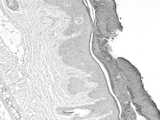

Fig. 3 is a model group histopathological examination image of example 1.

After the propranolol emulsion is applied to ears, the ears are flush, papules appear on the back of the ears, white psoriasis gradually increases along with the prolonging of the propranolol application time, the base is bright red, the surface is rough, the texture is hard, and the thickness is increased, as shown in figure 1; the negative group had no abnormality in the ear, as shown in FIG. 2; histopathological results show that the hyperkeratosis of the skin forms thicker scab, the granular layer is incomplete, the acantho layer is remarkably thickened, the epidermis extends downwards, the mastoid is elongated into a pestle shape, the number of new capillaries is increased to different degrees, and the blood vessels are congested, inflammatory cell infiltration and edema are changed, as shown in fig. 3; the ear skin of the guinea pigs in the negative group showed thin cuticle, granular layer, spinous cell layer, muscular layer and cartilage, and the hair follicles and sebaceous glands were observed, and the morphology of each layer was normal, and no pathological change was observed in the structure, as shown in fig. 4. The Baker score results of the ear tissues show that the model group 4.41 is significantly higher than the negative group by 0.98, and the difference is very significant and p is less than 0.01, which is shown in Table 2.